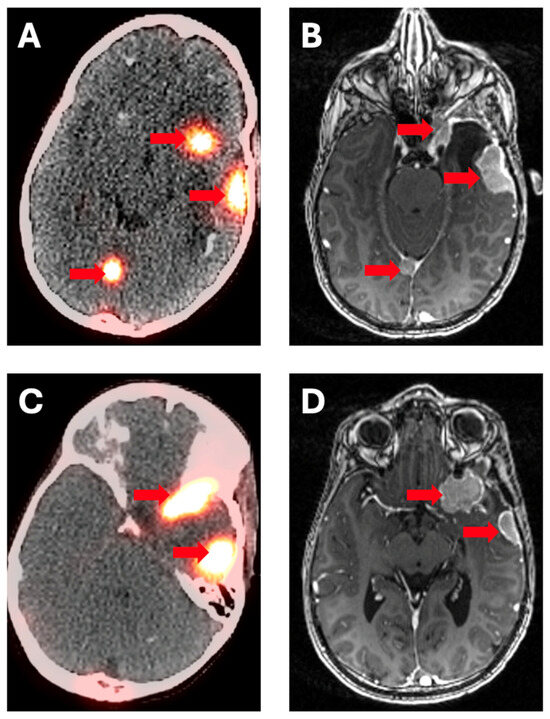

- Dressen, M.S.; Muthukrishnan, A.; Tragon, T.R.; Lieberman, F.S.; Mountz, J.M. Complementary Molecular and Metabolic Characterization of Meningiomas with DOTATATE and FDG-PET: Advancing Treatment Planning and Prognostication. Clin. Nucl. Med. 2019, 44, e26–e27. [Google Scholar] [CrossRef]